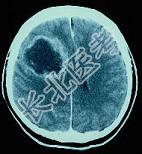

- [材料题] 女,54岁,发热,头痛,呕吐20天,左侧肢体无力6天,发病前有皮肤感染史,实验室检查:周围血象白细胞总数12.7×109/L,中性粒细胞0.76,核左移。

- 多项选择题1.颅脑CT见图,下列神经系统检查中,哪项对诊断颅内压增高有价值 ( )

- 多项选择题2.在定性诊断时最可能的诊断是 ( )

A、脑脓肿

B、恶性胶质瘤

C、脑包囊虫病

D、脑结核瘤

E、转移瘤